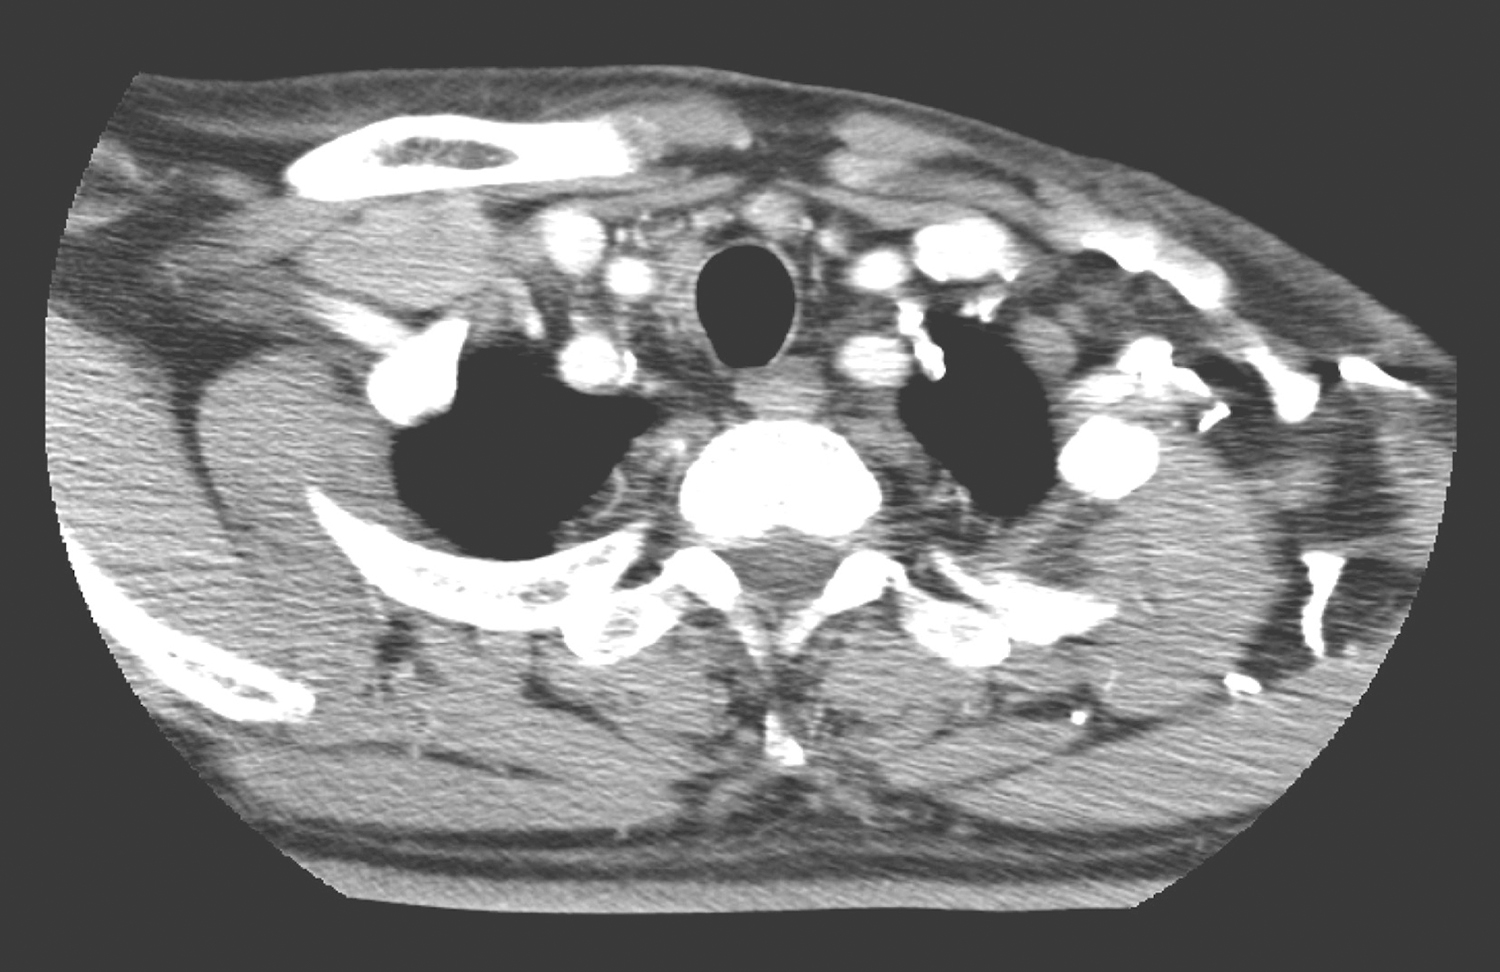

2.2013年10月10日,颈胸部CT检查所见:甲状腺左右叶内可见低密度结节,大者位于右叶,约1.6cm×1.2cm,其内可见高密度灶(图3)。扫描范围内鼻窦、鼻咽、口咽未见明确异常。

双颈深、右下颈甲状腺旁、双侧锁骨上、气管前、可见多发淋巴结肿大,部分明显强化,大者约1.2cm×0.9cm(图4~图6);余颈未见明显肿大淋巴结。

图3 颈部CT示甲状腺左右叶内低密度结节

图4 颈部增强CT示右颈肿大淋巴结

图5 颈部增强CT示双颈多发肿大淋巴结

图6 颈部增强CT示气管前及锁骨上肿大淋巴结